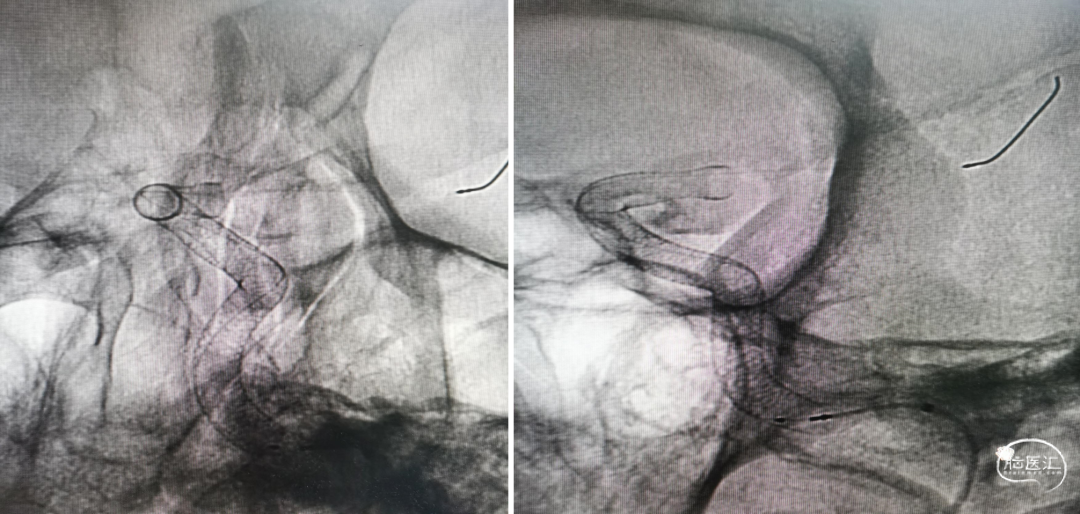

利用微导丝、微导管对支架进行按摩;行Xper CT HiRes Cran.Stent扫描评估。

术中造影

Xper CT HiRes Cran.Stent